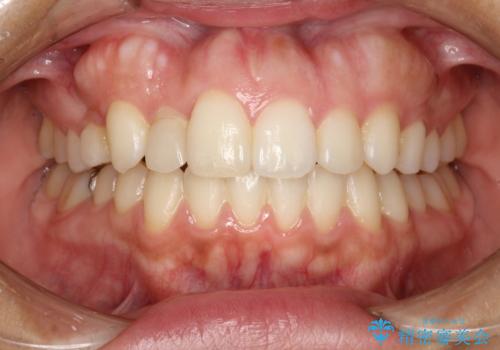

前歯のステイン(着色)をPMTCでキレイに

- コーヒーを普段からよく飲むため、着色・ステインが気になるとのことで来院されました。着色が前歯のみに付着していたためPMTC自費クリーニングの30分コースを行いました。

- 5千円+tax費用は治療当時の料金となります